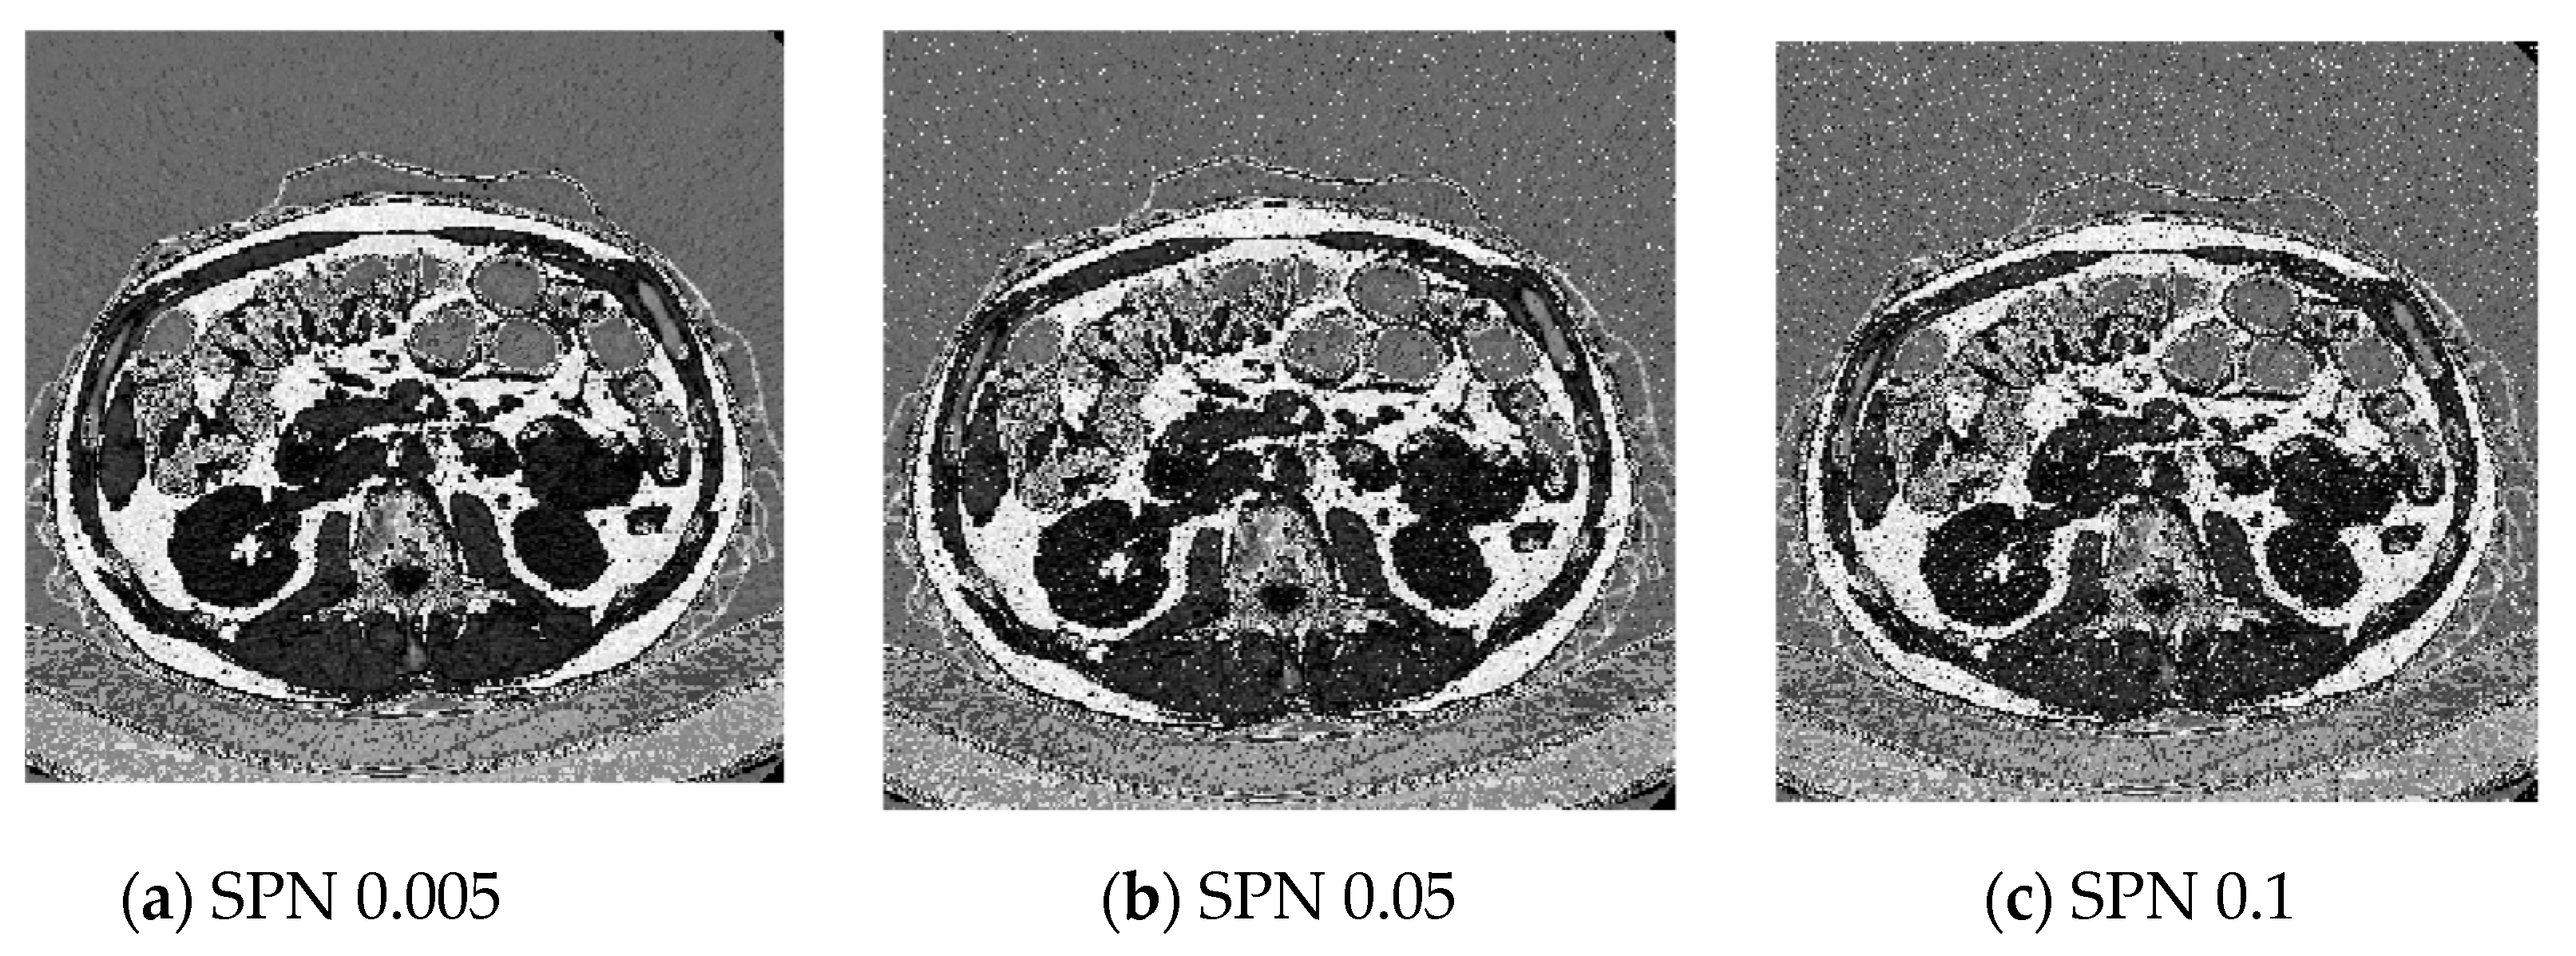

5.5. Image with Noise Analysis

To evaluate the effectiveness of the suggested approach, an image with adjustable noise parameters—both mean and variance—is utilized. This allows for an assessment of how varying levels of degradation impact on the method’s ability to encode the image while minimizing data loss. In this analysis, a lung image serves as the benchmark for testing the proposed technique. Figure 11 presents the encoded image subjected to Salt and Pepper Noise (SPN) with noise variances of 0.005, 0.05, and 0.1. The corresponding PSNR values, which are detailed in Table 9, indicate that (1) our encoding algorithm demonstrates significant robustness against SPN, maintaining PSNR values above 5.8 dB, and (2) the reconstructed images retain superior visual quality. These results confirm the method’s strong resistance to noise-induced distortions.

Figure 11.

Decrypted images under different noises with different variances.

Table 9.

Image with difference noise addition.